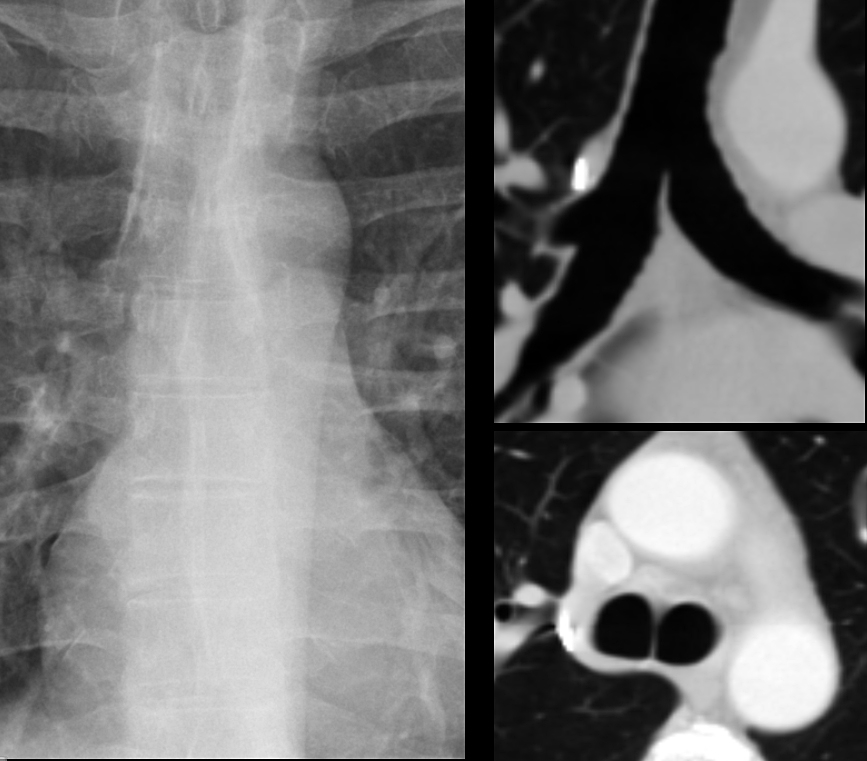

Carina